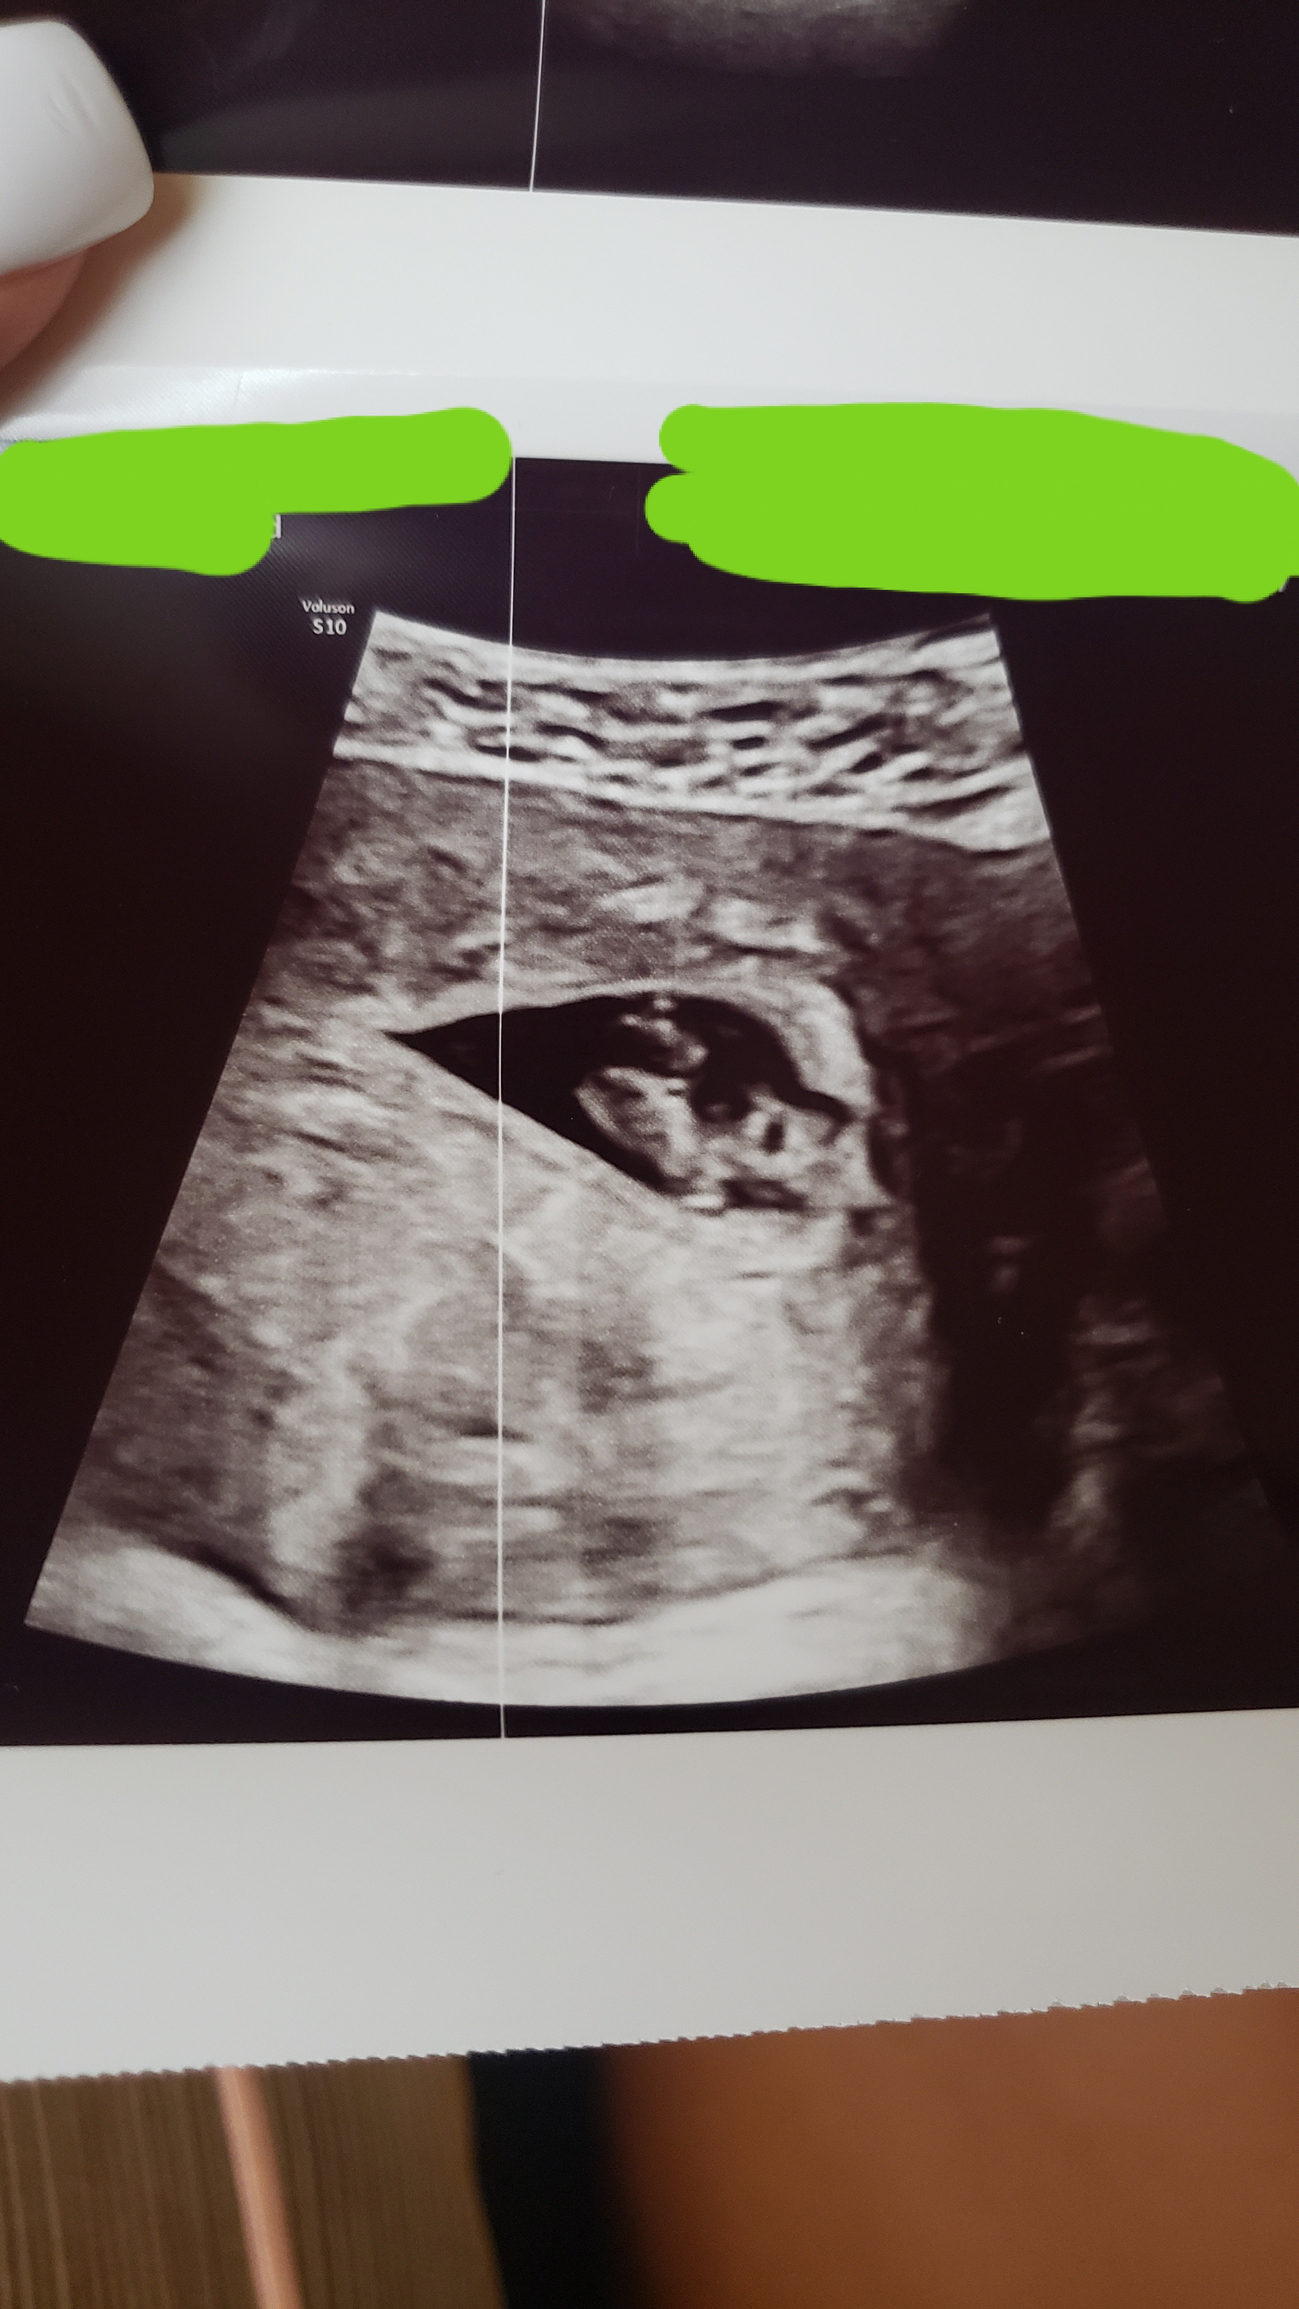

Can anyone help me out with my 8 week ultrasound pic (abdominal)? I've tried to figure this theory out but I don't understand what I'm looking at apart from the baby lol. I'm just curious how this works lol.